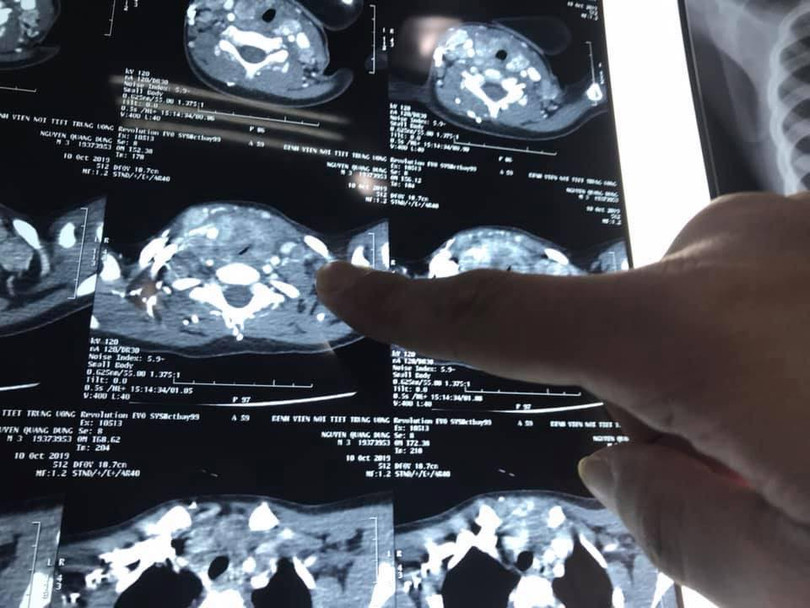

| Ảnh chụp CT khối u của bé D. |

PGS.TS Trần Ngọc Lương - Giám đốc Bệnh viện Nội tiết Trung ương - nhận định, bé D. là trường hợp mắc ung thư tuyến giáp nhỏ tuổi nhất được phát hiện tại Bệnh viện. Ung thư đã di căn nhiều ở hạch cổ 2 bên của D., còn khối u tuyến giáp phát triển lớn chèn ép khí quản gây khó thở.

Bên cạnh đó, do mức độ di căn lan rộng vào dây thần kinh, tĩnh mạch cảnh và khí quản, khối u gây đè bẹp khí quản nên quá trình gây mê cho bé D. rất khó khăn. Ngoài ra, việc sử dụng liều lượng thuốc cùng cần được cân nhắc kỹ lưõng.